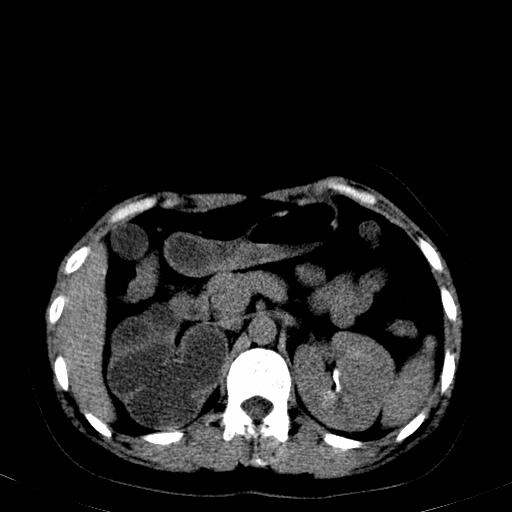

患者体检发现右肾体积增大,怀疑右肾积水

右肾多发囊肿,左肾、左输尿管结石

右肾重度积水,以肾盏积水明显,有分隔,上段输尿管轻度扩张,管壁增厚,考虑肾结核可能,请结合尿检查,胸部拍片排除肺结核。

右侧肾积水、左侧肾结石

右侧肾积水、左侧肾结石  ,要排除右肾结核可能。

右肾重度积水,建议ct向下扫描或逆行造影,左肾及左输尿管结石 .

1)不排除右肾结核可能。2)左肾及左输尿管上段结石?